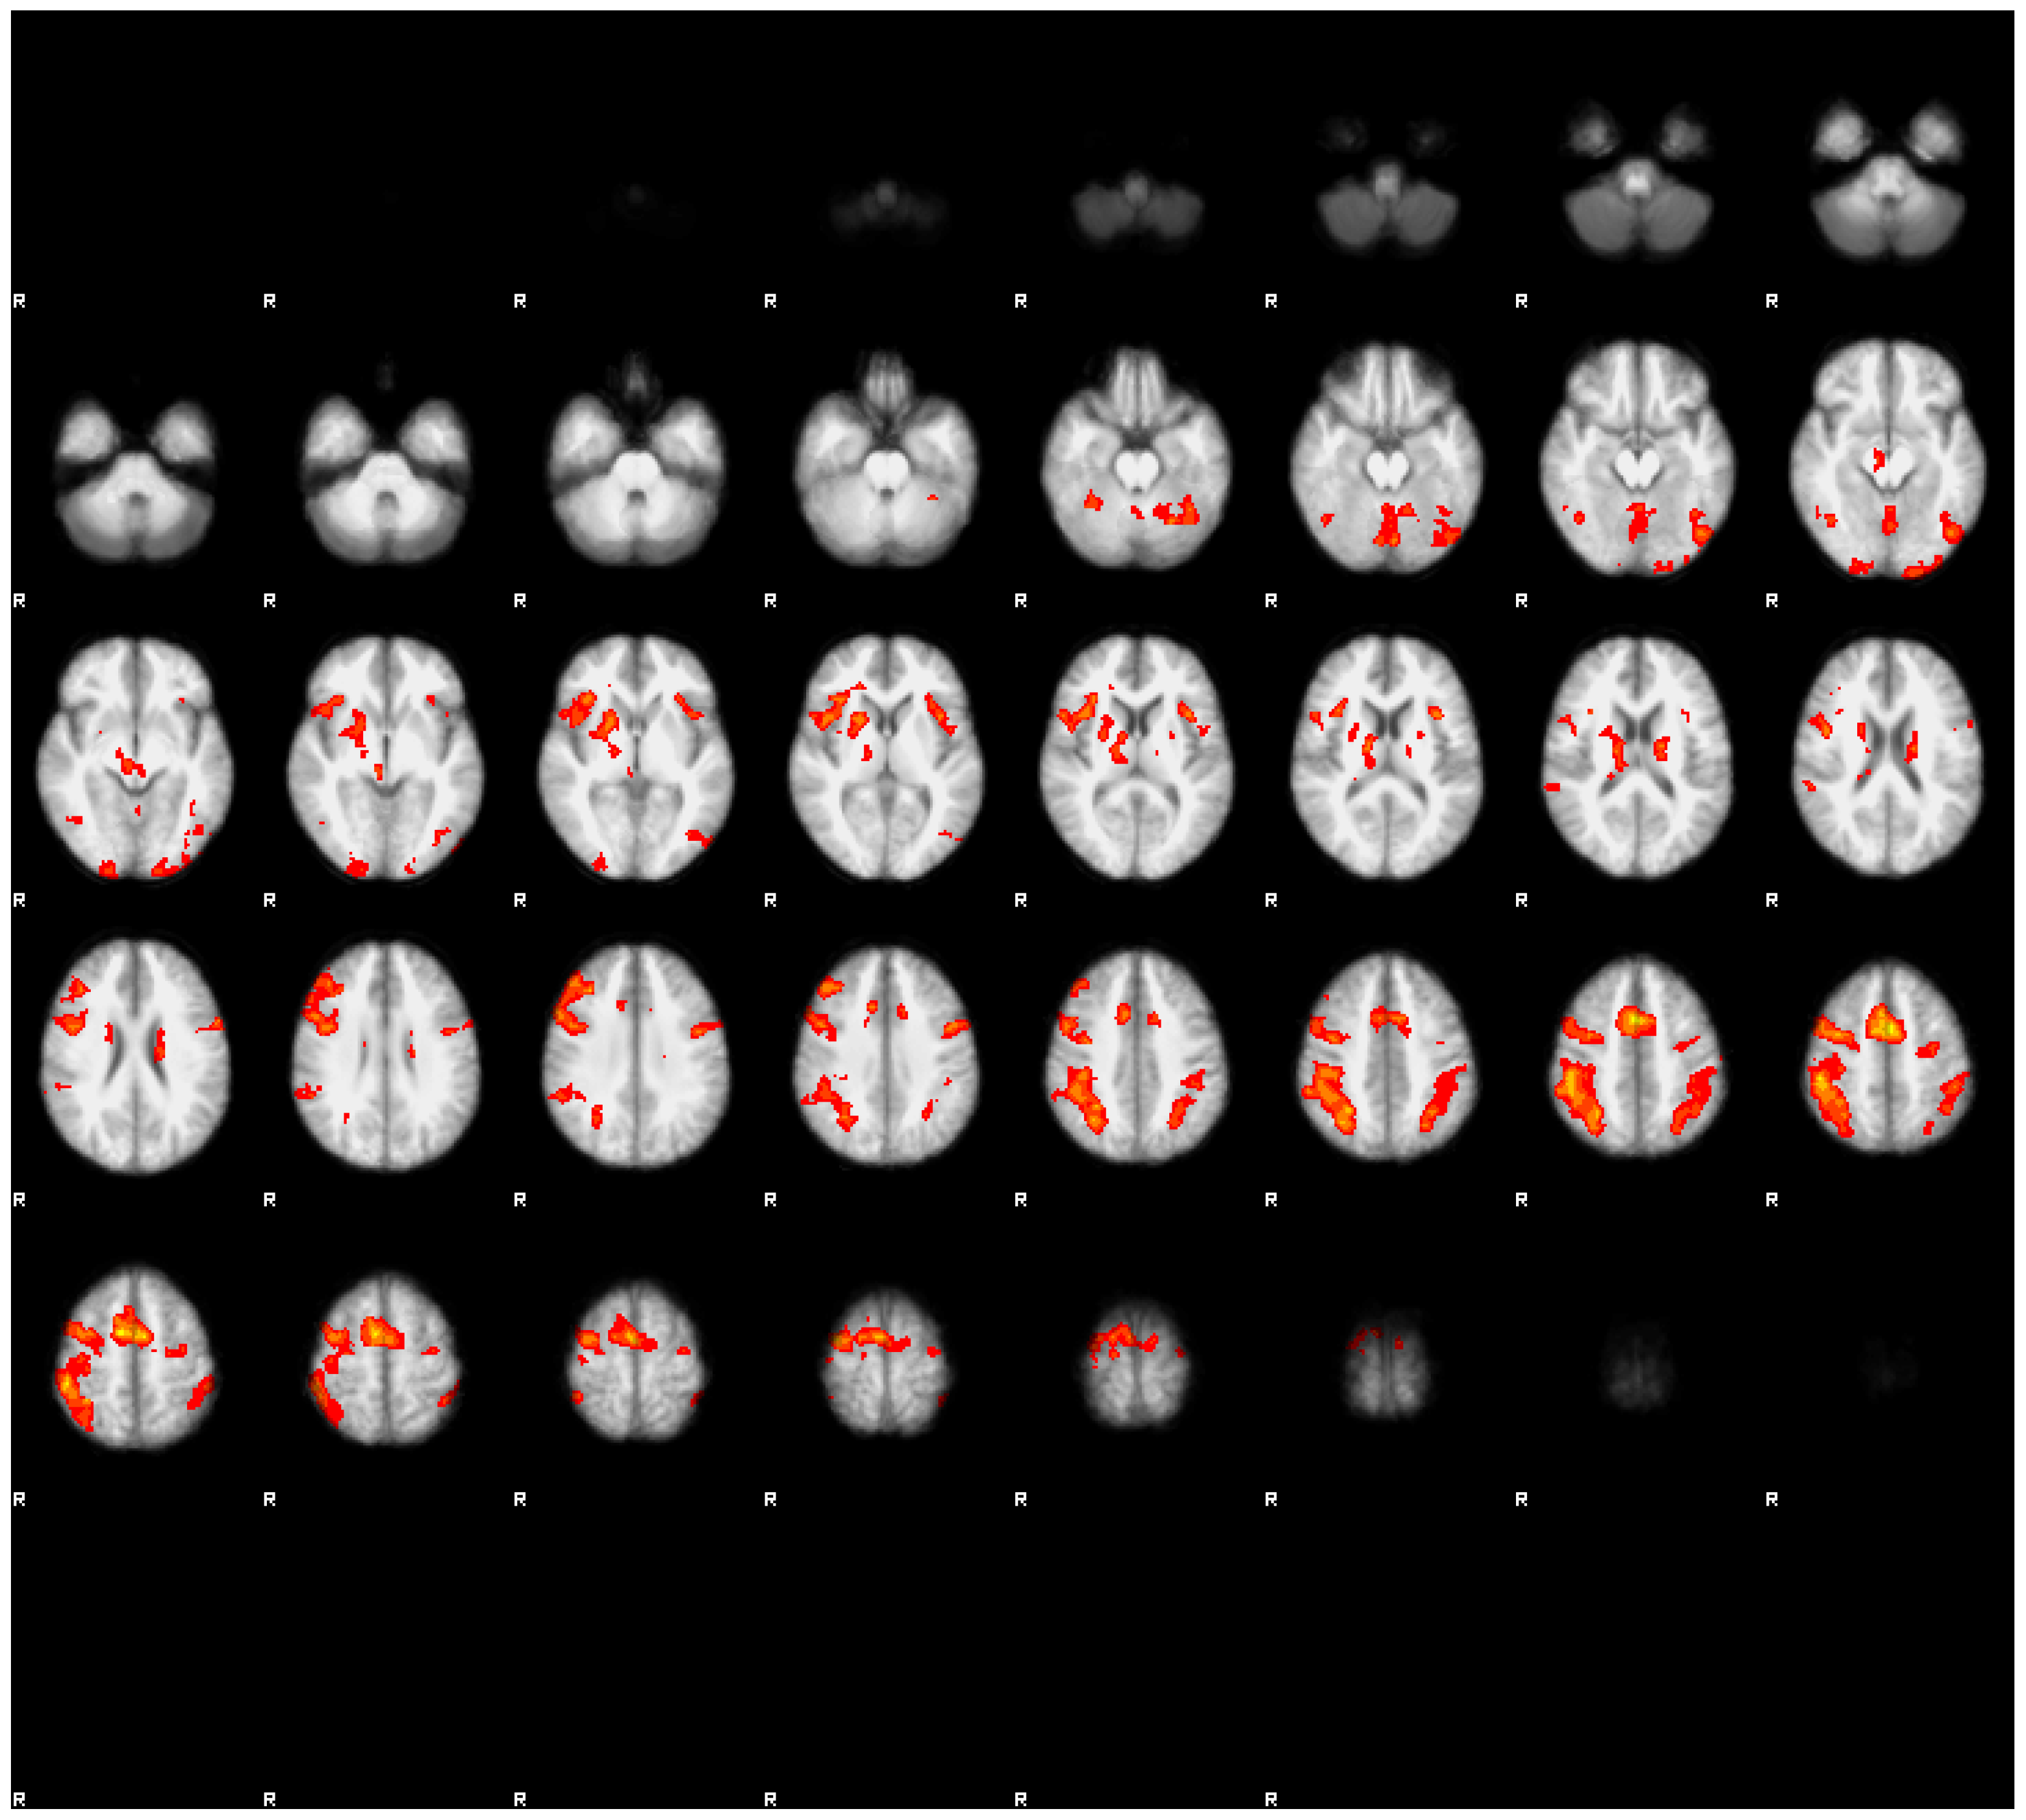

3.3.1. Main Effects of the Task in Both Conditions

The results are displayed in Figure 2 and Figure 3, as well as presented in Table 3 and Table 4. In both conditions, we observed a mostly overlapping pattern of activations in the lateral frontal, lateral parietal, and medial frontal regions. In both conditions, we also observed overlapping clusters in the left lateral temporo-occipital regions. There were marked differences between both conditions. In the rested condition, the general extent of suprathreshold activation was notably wider and more bilateral than in the fatigued condition. The strongest effects of task in the rested condition were observed in the posterior parietal cortex, as well as in the premotor cortex, extending into the dorsolateral cortex, mainly in the right hemisphere. Bilateral activations were also observed in the anterior insulae and in the medial frontal regions (SMA). In contrast with the fatigued condition, we observed bilateral activations in the polar visual cortex, as well as in the fusiform gyrus.

In the fatigued condition, the extent of the suprathreshold clusters was notably smaller. Bilateral activations were seen only in the parietal regions, while in the frontal regions, the activations were mainly observed in the right hemisphere. In neither condition were the activations correlated with the reaction times.

Figure 2. The main effects of the task in the rested condition. Images were thresholded at Z > 3.1. Note the extensive bilateral activation in the posterior parietal cortices, SMA, premotor cortex, and dorso-lateral prefrontal cortex. Activation in the middle temporal cortex was left-lateralized. The right side of the brain is denoted by letter R.

Energies 14 05409 g002